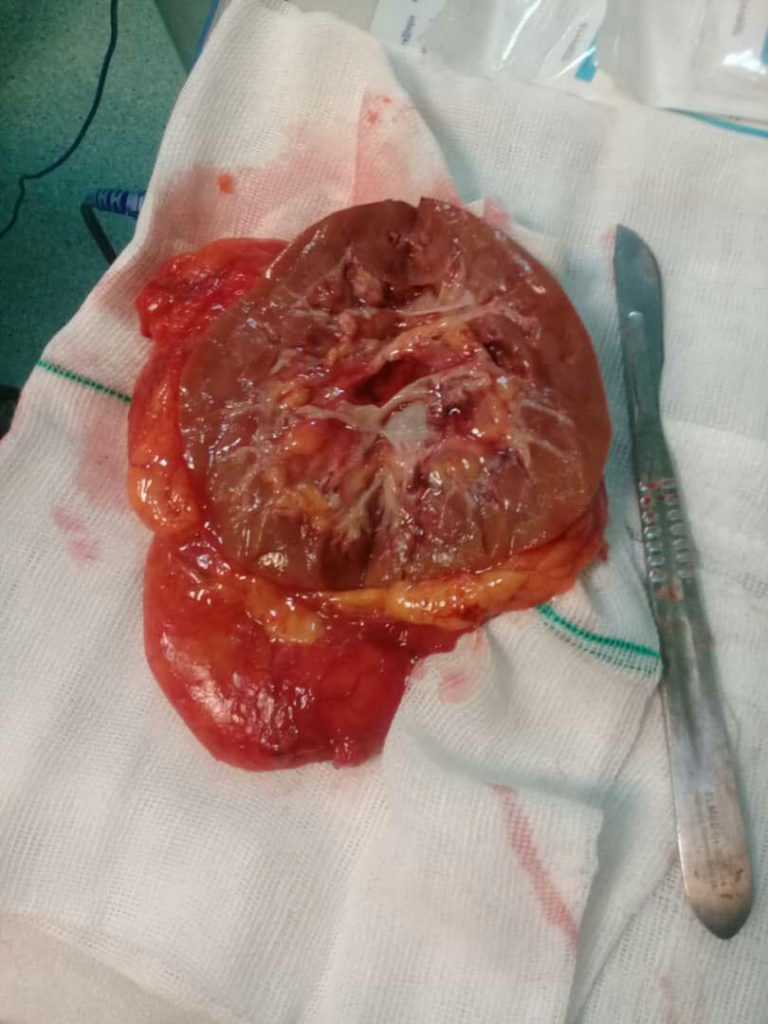

جراحی سنگ به روش بسته و PCNL

- معالجه سرطان مثانه، کلیه ها، بیضه ها، آلت تناسلی، غدد فوق کلیه و پروستات در مردان

- درمان سنگ کلیه

- اقدامات درمانی سرطان مثانه، کلیه ها و غدد فوق کلیه

- از بین بردن سنگ کلیه